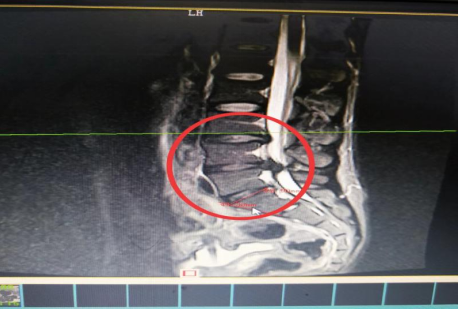

10分鐘后,患者肖先生沒(méi)有家屬陪同的情況下被緊急到骨科一區(qū)病房接診滿頭大汗、非常緊張肖先生,舒小林醫(yī)師仔細(xì)詢問(wèn)了病情。原來(lái)肖先生從事搬運(yùn)行業(yè),半年前就腰腿痛就醫(yī),當(dāng)時(shí)在保守治療后稍有緩解,沒(méi)有引起重視直到11月13日下午因搬重物后突然感到腰腿劇烈疼痛、麻木、大小便困難,這才120急救電話。骨科一區(qū)錢(qián)軍副主任舒小林醫(yī)師立即給患者作了詳細(xì)的體查,并立即聯(lián)系做急診腰椎磁共振確定有無(wú)神經(jīng)受壓。腰椎磁共振結(jié)果提示:腰4/腰5椎間盤(pán)膨出,導(dǎo)致馬尾神經(jīng)嚴(yán)重受壓,有明顯的手術(shù)指征,如不盡快手術(shù)會(huì)致神經(jīng)受損難以恢復(fù)。錢(qián)軍副主任來(lái)到肖先生病床前,將手術(shù)方案、手術(shù)風(fēng)險(xiǎn)及并發(fā)癥詳細(xì)告知肖先生本人,肖先生表示同意并簽字馬上手術(shù)。